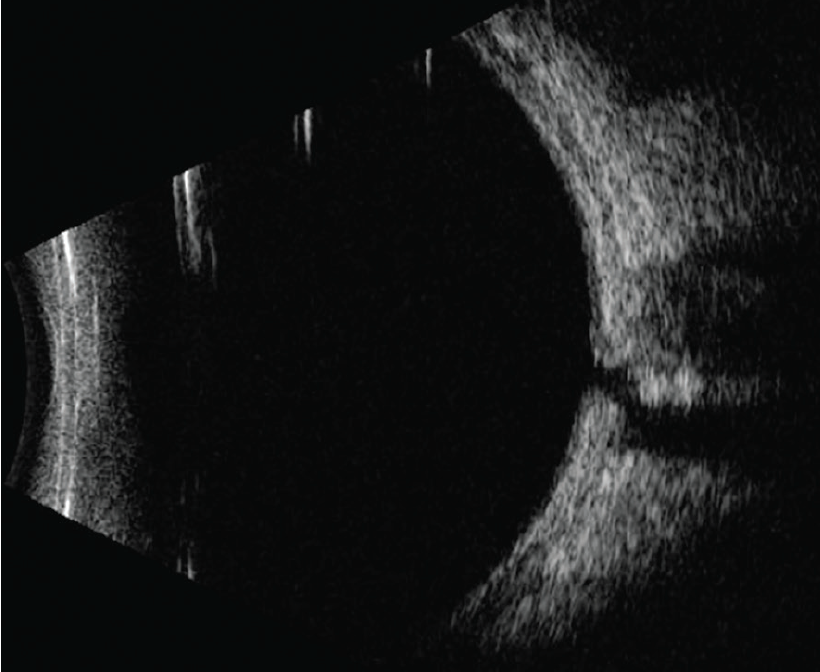

Histopathologically, ODP appears as a herniation of dysplastic retinal tissue into a collagen-rich excavation that can extend into the subarachnoid space through a defect in the lamina cribrosa (Figure 3).7 Studies of ODP using OCT have revealed connections between the subretinal and intraretinal space, the perineural space, and the vitreous cavity (Figure 4).8

<p>Figure 3. ODP appears as a herniation of dysplastic retinal tissue into a collagen-rich excavation that can extend into the subarachnoid space through a defect in the lamina cribrosa.</p>

Figure 3. ODP appears as a herniation of dysplastic retinal tissue into a collagen-rich excavation that can extend into the subarachnoid space through a defect in the lamina cribrosa.